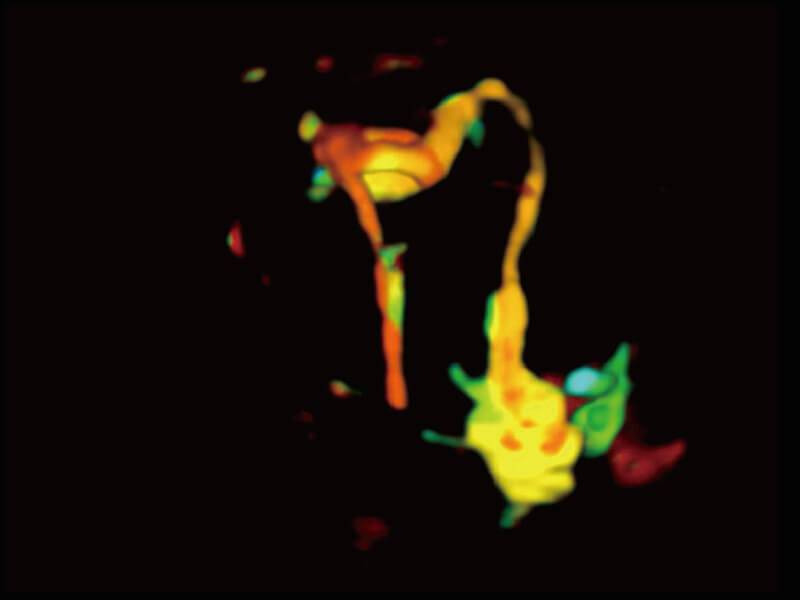

成像功能

S60创新的探头工艺、高精度模数转换系统、前沿的波束重建技术,从前端信号处理每一个环节采集无损声学数据,真实还原组织原貌,再现解剖细节。